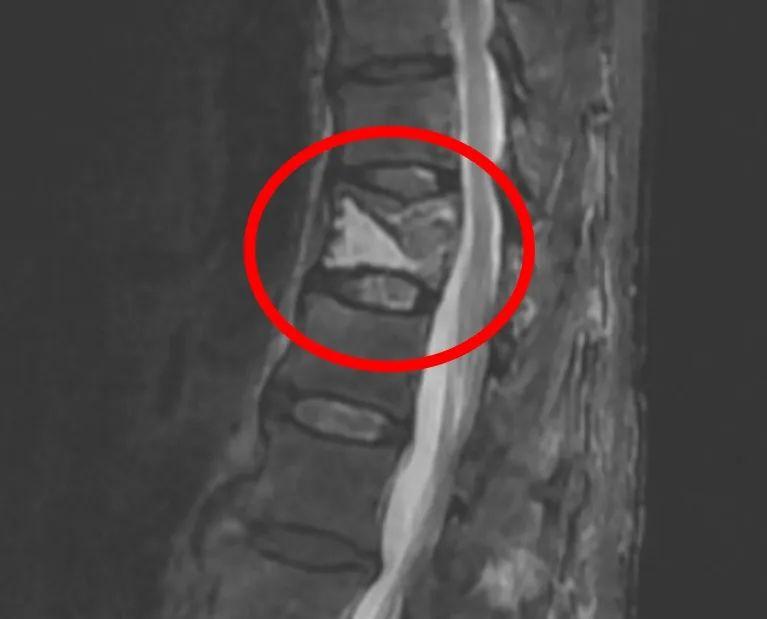

经检查,医生发现周阿姨的腰椎出现“真空裂隙征”,这是椎体缺血坏死的典型表现。最终,周阿姨被确诊为Kummell病(迟发性创伤后椎体骨坏死),由于其椎体缺血坏死导致假关节形成,宁大一院神经脊柱外科卢斌主任医师为她实施了微创骨水泥强化手术,术后她的症状终于得以缓解。

据了解,Kummell病常见于严重骨质疏松的老年人,常因轻微外伤(如跌倒、咳嗽)导致椎体骨折。早期骨折后血液供应中断,骨头内部逐渐“干枯”,但表面暂时稳定,可能仅轻微疼痛;到达中期,也就是数月后,缺血坏死的骨头开始塌陷,形成“空洞”(影像学表现为“真空裂隙征”);晚期时椎体完全变形,压迫神经,引发剧烈疼痛甚至脊柱后凸畸形(驼背)。